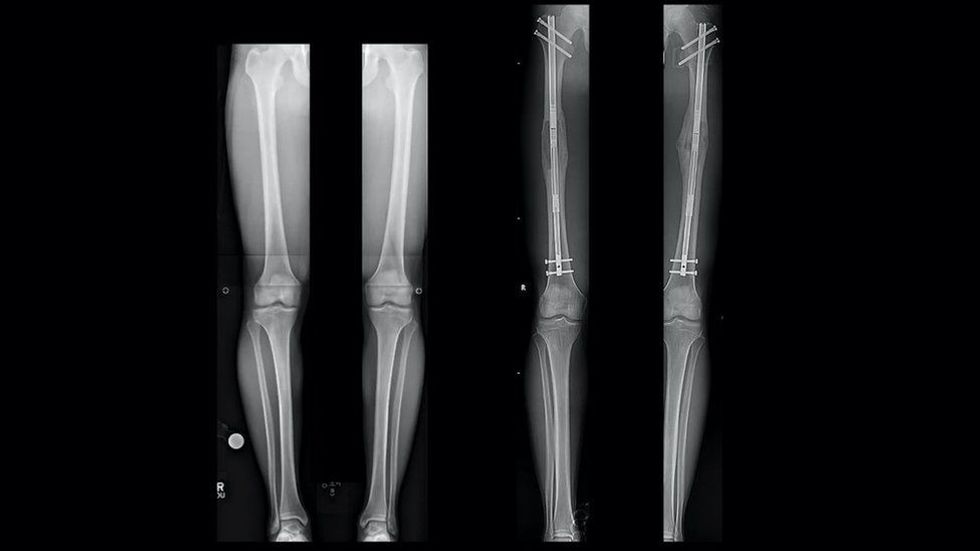

Vendosi të shtrihet në spital që ta zgjidh këtë problem në shtratin e sallës së operacionit - në vitin 2015 nga 162 centimetra sa i kishte, arriti të bëhet 170 centimetra falë ndërhyrjes kirurgjikale.

Zgjatja e këmbëve përmes ndërhyrjeve kirurgjikale mund të kryhet në dhjetëra shtete, ku disa pacientë madje arrijnë të rriten për 13 centimetra. Derisa është e vështirë të thuhet se sa njerëz në vit i nënshtrohen ndërhyrjeve të tilla, klinikat po fitojnë çdo ditë e më shumë popullaritet.